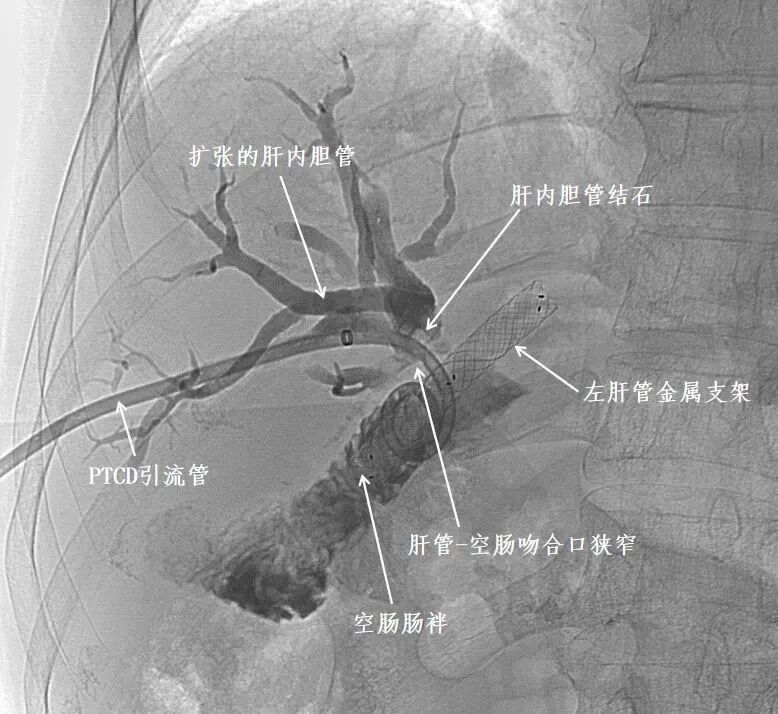

文先生两年前在外院接受了肝门部胆管癌根治术,该手术包含胆肠吻合术,但术后反复出现腹痛、寒战高热和黄疸,多次穿刺引流(经皮肝胆管穿刺置管引流,PTCD)和胆道支架置入术均效果不佳,在家人的陪同下,来到我院肝胆胰外科就诊,经PTCD管造影发现胆肠吻合口附近胆管多发结石。肝胆胰外科果断安排文先生手术,直接利用原引流管窦道扩创置入鞘管,硬质胆道镜下行胆管探查,真相终于浮出水面——原胆肠吻合口处竟残留大量不可吸收血管缝线。这些缝线成为“异物核心”,周围形成絮状物和结石堆积,导致吻合口狭窄,引发反复感染。

PTCD管造影发现吻合口附近胆管结石